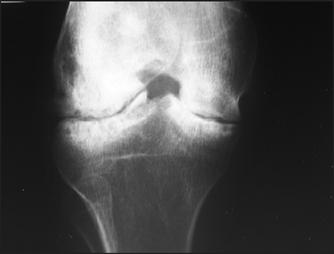

Figure 26.5 Haemophilia X-ray of the knee showing loss of joint space and some deformity of the adjacent bone. Although the tibia and femur are sclerotic adjacent to the destructive change, the bones are generally osteopenic with mild overgrowth of the epiphysis. Ask about the consequences of arthritis.